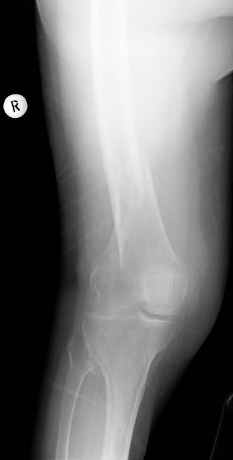

Видно спиральный перелом дистального метадиафиза бедра. У нас бы сделали антеградный закрытый интрамедуллярный остеосинтез.

>Попробуяю угадать - ретроградный гвоздь?

Вы угадали.